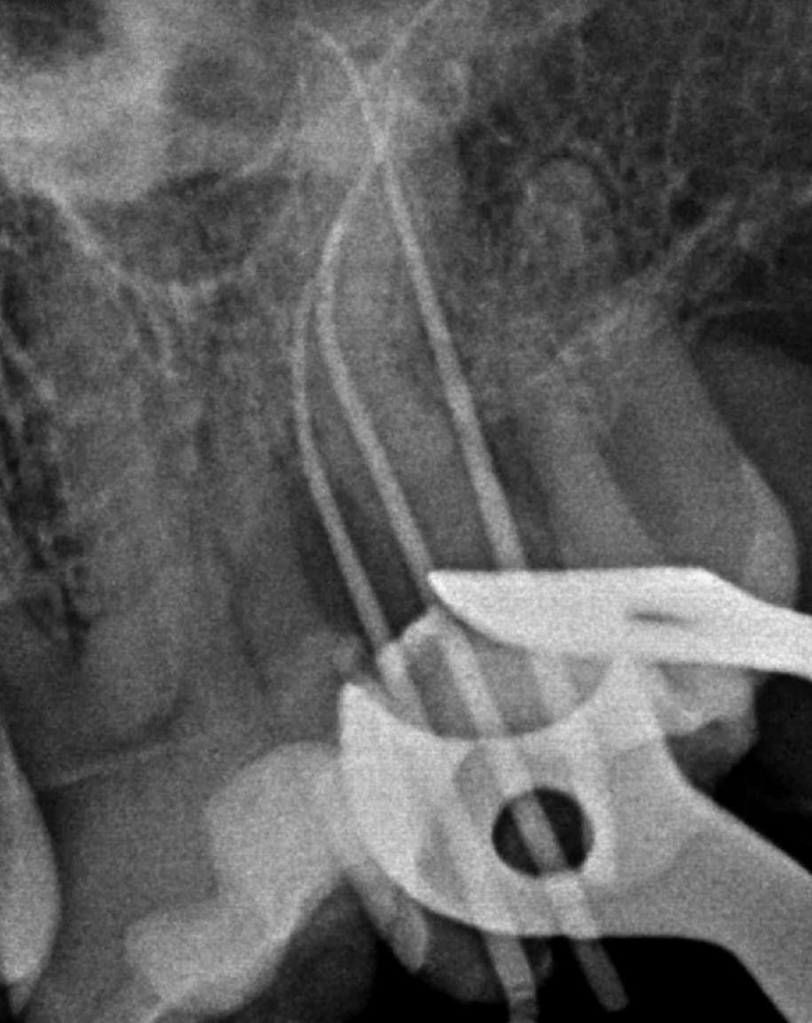

Molar superior anatomía compleja